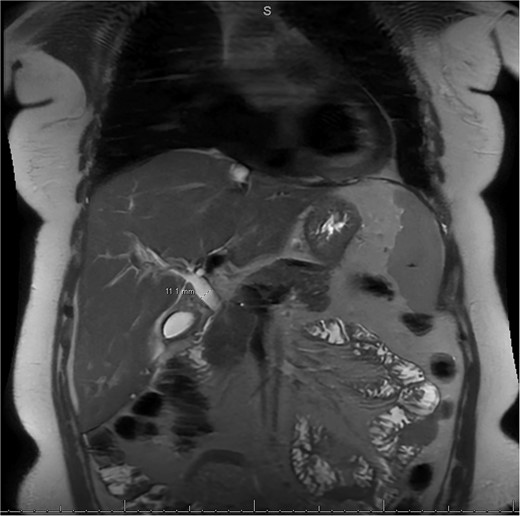

MRI/MRCP from second hospitalization demonstrating CBD of 1.1 cm.

A 49-year-old female with a history of ADPKD and multiple liver cysts, 13-months status post subtotal cholecystectomy, endoscopic retrograde cholangiopancreatography with biliary sphincterotomy and balloon stone extraction, presented to the emergency department with fever and a 4-day history of discomfort in the right upper quadrant. At the time of the initial cholecystectomy, total cholecystectomy could not be performed due to extensive adhesions, and subtotal cholecystectomy with complete evacuation of the stones was done instead. Magnetic resonance cholangiopancreatography (MRCP) done at that time showed a dilated common bile duct (CBD) to 1.5 cm, intra and extrahepatic biliary dilatation, multiple liver cysts measuring up to 2 cm, and multiple stones in the CBD, including at the level of the ampulla (Fig. 1). Computerized tomography scan at the time of the second admission showed acute cholecystitis and she had mildly elevated transaminases, but there was no evidence of cholestasis or pancreatitis. MRCP showed minor proximal intrahepatic biliary dilation and cholelithiasis but no duct calculi (Figs 2–4). A laparoscopic cholecystectomy was attempted with extensive adhesiolysis between the gallbladder and surrounding omentum and mesocolon, but the cystic duct could not be isolated, and ultimately the cased was converted to open. While removing the gallbladder in a top-down fashion, a small bile leak was identified right at the closed end of the gallbladder remnant, where the bile duct was adhered to the gallbladder wall. Intraoperative cholangiogram was obtained through a small perforation in a right posterior bile duct at the site of attachment, which showed right posterior, right anterior and left hepatic ducts of equal size converged at a trifurcation (Fig. 5). The duct was repaired over a T-tube and observed throughout the rest of the case and no bile leak was identified. The gallbladder was opened along its lateral edge, revealing a hugely dilated cystic duct with ~10 to 12 marble-sized stones packed within the gallbladder remnant and cystic duct down to the juncture with the common bile duct. All the stones were removed and the safe portion of the gallbladder remnant was resected leaving the side attached to the bile duct in situ due to the Mirizzi anatomical variant. The cystic duct was oversewn along with the remnant of the gallbladder wall. Pathology showed acute-on-chronic cholecystitis with cholelithiasis. Repeat MRCP showed no retained stones in the biliary tree. The recovery course was unremarkable.